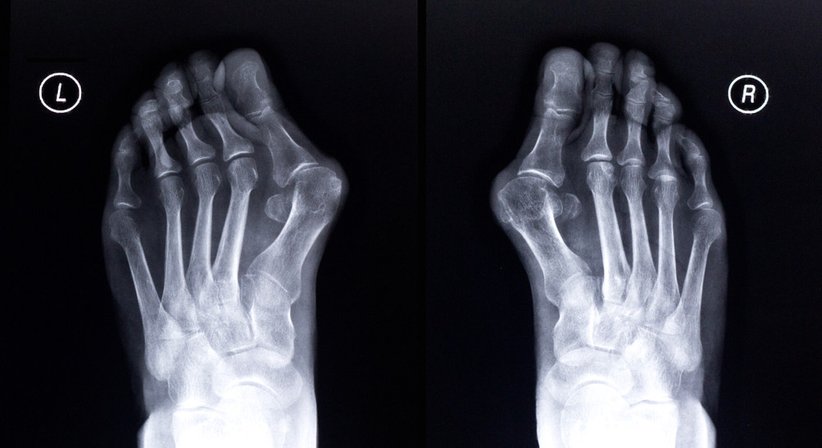

Fußchirurgie

·      Hallux valgus